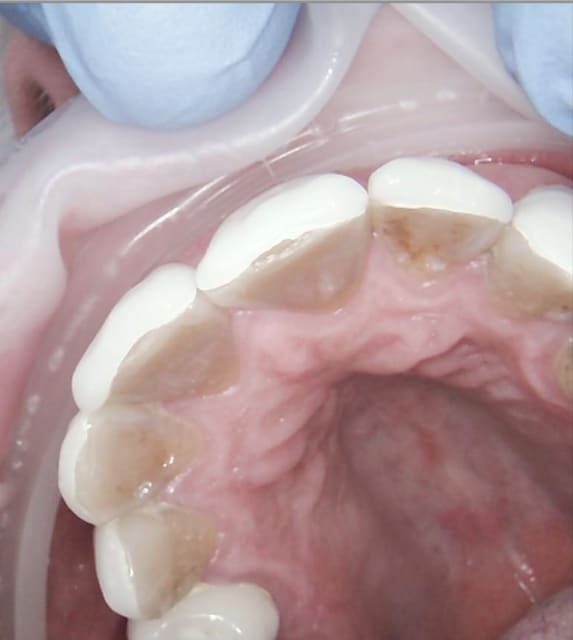

J'avais du les passer déjà quelque part ici. Travail fait en une journée sur 10 dents. J'ai perdu la photo avec écarteur du travail fini, mais cela tombe bien car j'avais pas un très bon maquillage des collets. Ceci dit, patiente AVC avec sourire comme tu vois.

A3 zaw6gr - Eugenol

A7 kn2z0z - Eugenol